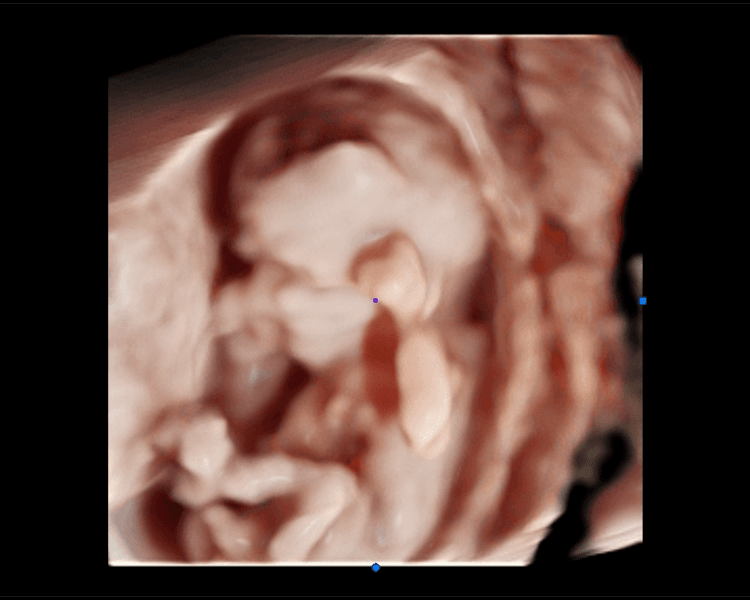

La Ecografía Inicial (Confirmación de Embarazo), es el primer paso para confirmar tu embarazo de manera segura y precisa. A través de esta ecografía, podrás verificar la ubicación del embarazo, el latido del corazón fetal y la correcta evolución de tu bebé desde el inicio. Es una experiencia tranquila, no invasiva, que te proporciona la certeza que necesitas en las primeras semanas. ¡Reserva tu cita y confirma con nosotros el inicio de este hermoso viaje!